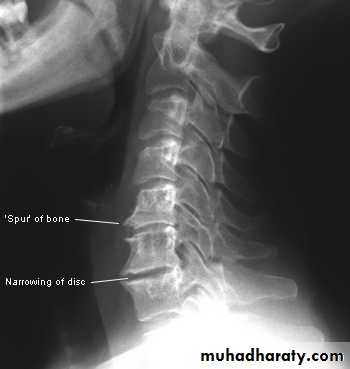

X-rays: show an abnormal narrowed disc space and to exclude bone diseases. After several attacks the disc space may be narrowed and small osteophytes appear.CT and MRI are more reliable than myelography.

X-Rays:

Flattening of the disc space and marginal osteophyte formation appear later.• CHRONIC INTERVERTEBRAL DISC DEGENERATION